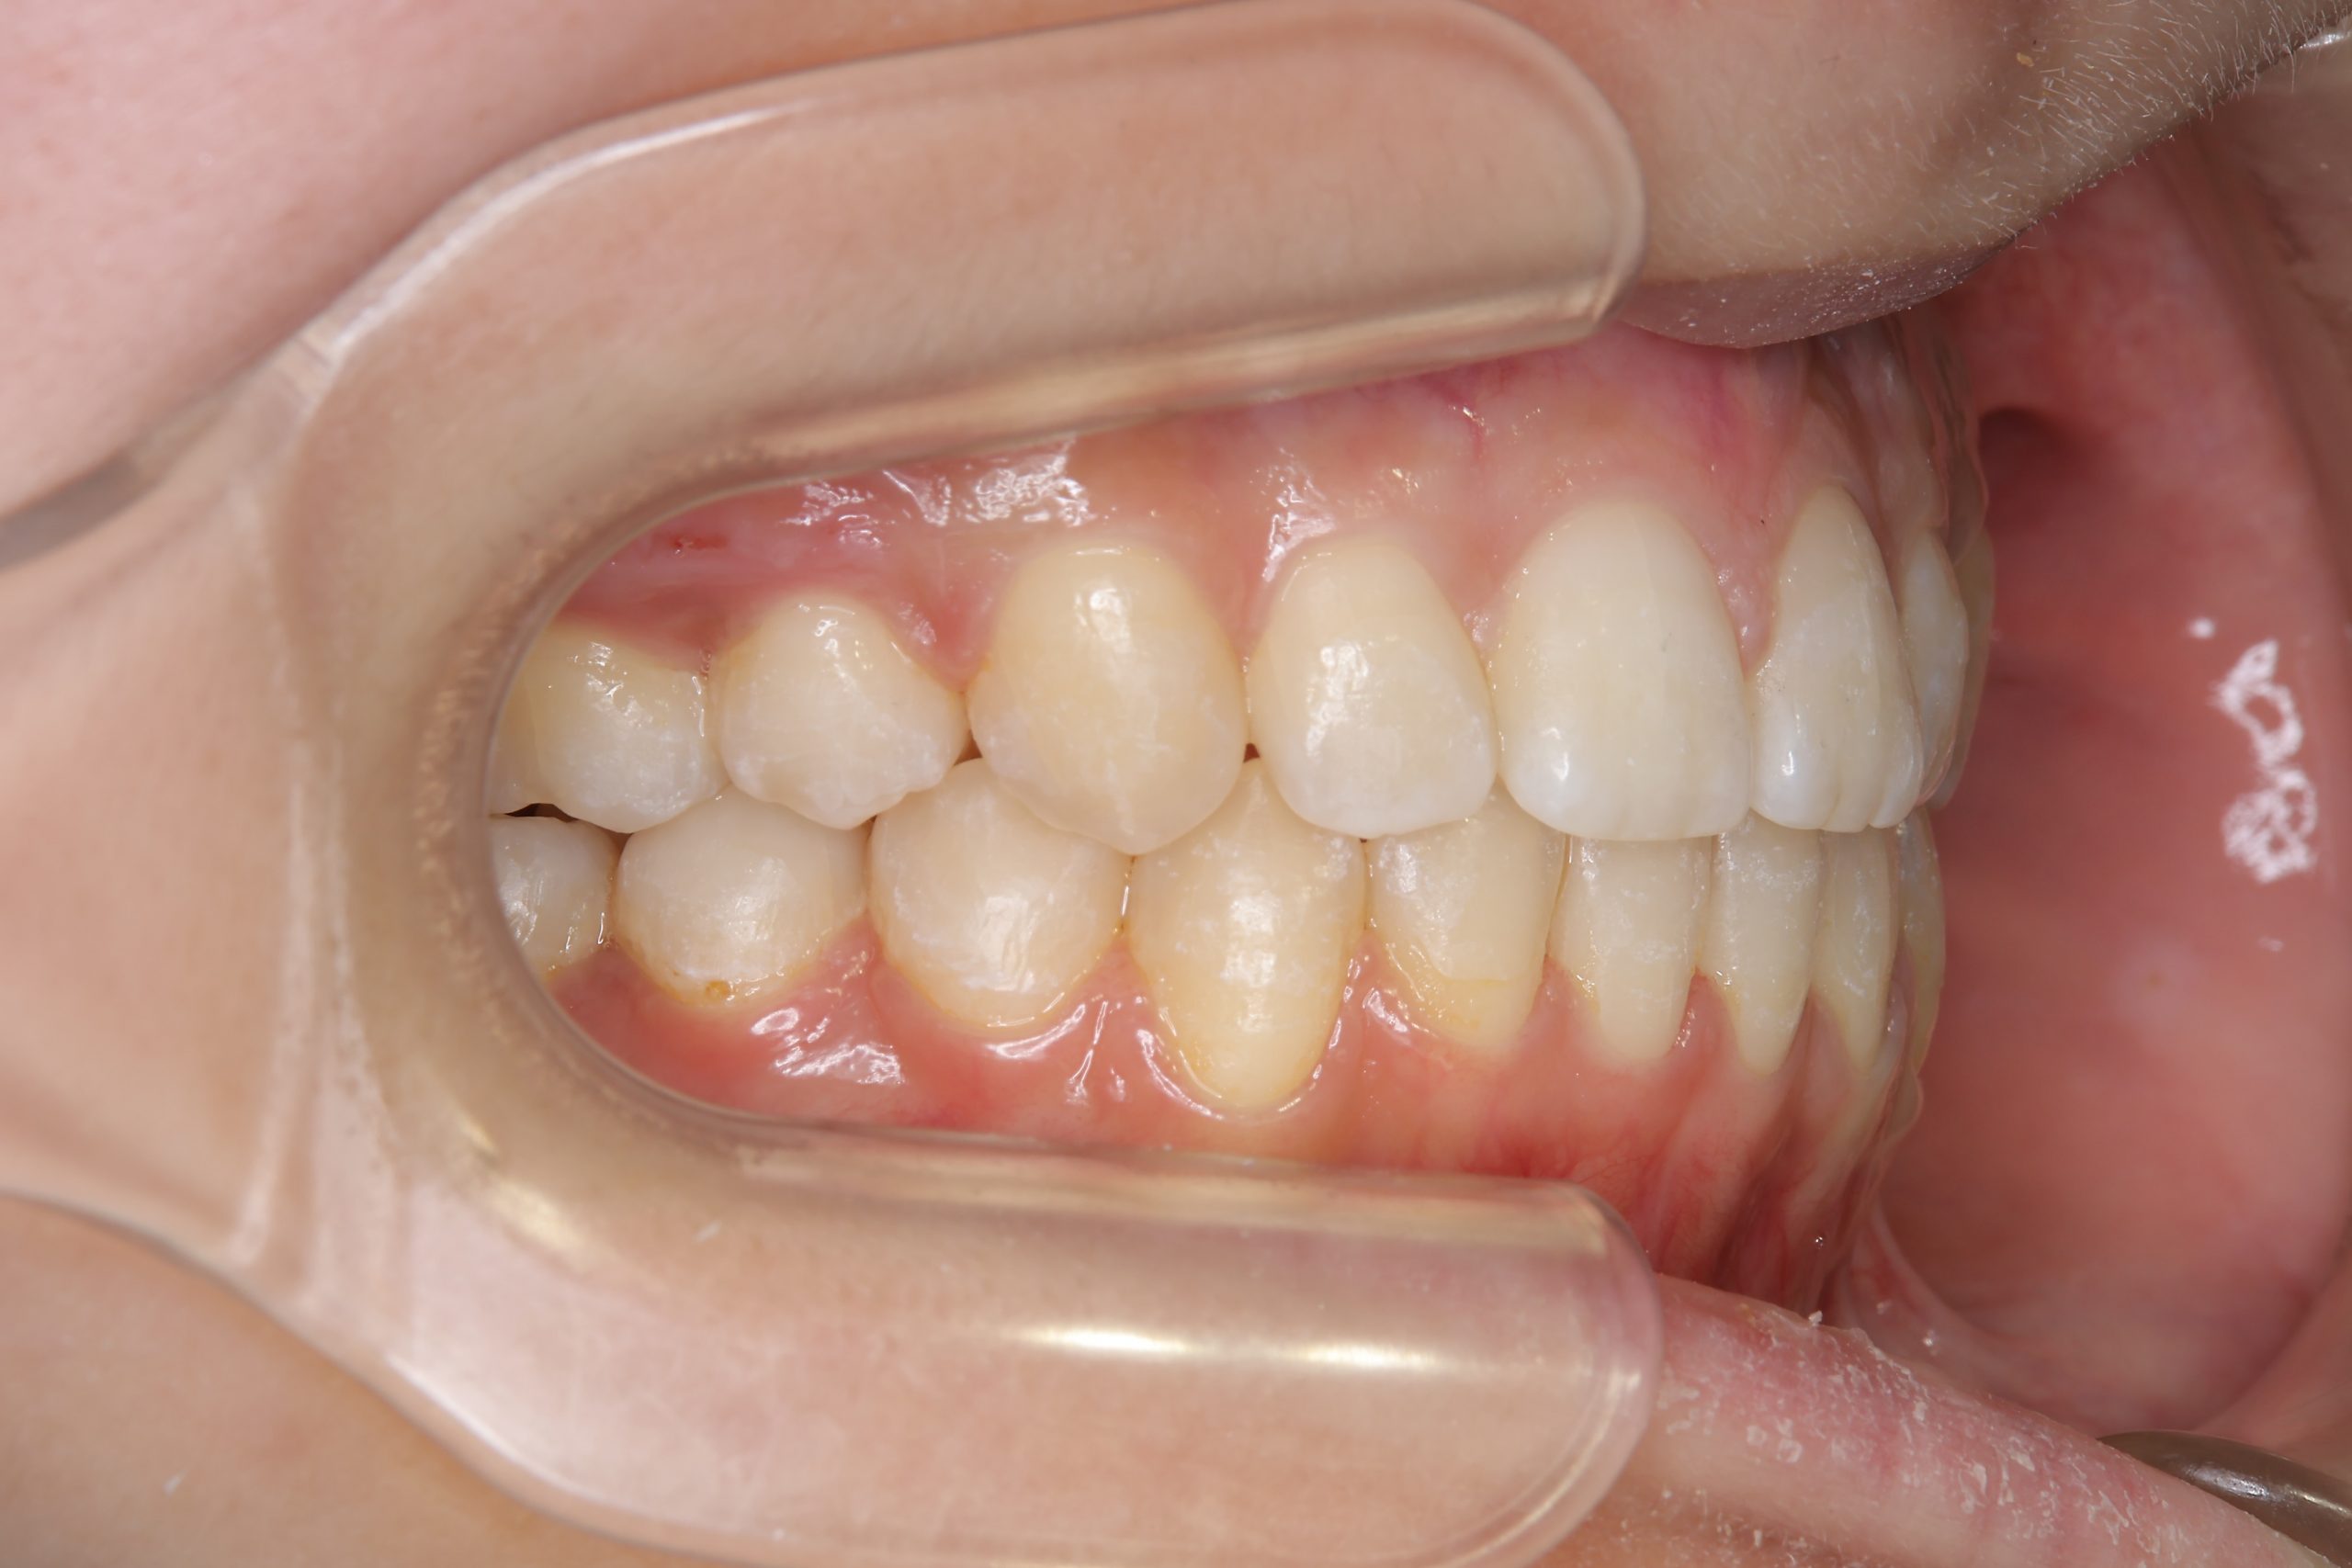

ビフォー

全顎ワイヤー矯正 症例_418

主訴 歯並びがガタガタ ※抜歯あり

施術内容 成人矯正1期治療

治癒期間 2年10か月間

費用 1,069,200円(税込)